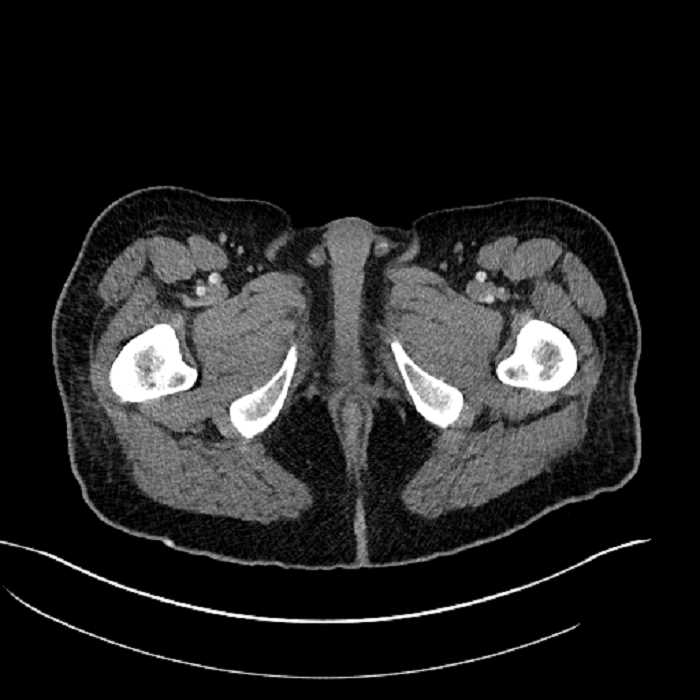

• High grade stenosis of the left common iliac artery, with the left internal and external iliac arteries remaining patent

• Ankylosis of both sacroiliac joints

High grade stenosis of the left common iliac artery. The left external and internal iliac arteries are patent.